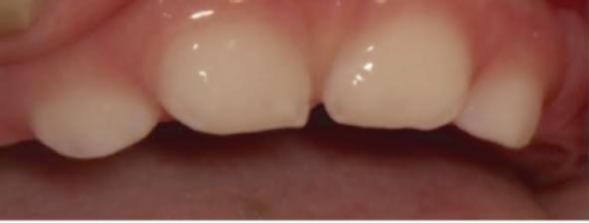

4) Διαταραχές οδοντοφυίας και ατελή οδοντογένεση ορατές ήδη από τη βρεφική ή παιδική ηλικία, πρόωρη απώλεια νεογιλών ή ενήλικων δοντιών, σοβαρή τερηδόνα.

Τέλος, η οδοντοϋποφωσφατασία περιλαμβάνει πρόωρη απώλεια νεογιλών δοντιών και / ή σοβαρή τερηδόνα (εικόνες 8, 9). Σπάνιες περιπτώσεις βρεφών με υποφωσφατασία που έχουν φυσιολογική δράση αλκαλικής φωσφατάσης στον ορό θεωρούνται ότι πάσχουν από «ψευδοϋποφωσφατασία».